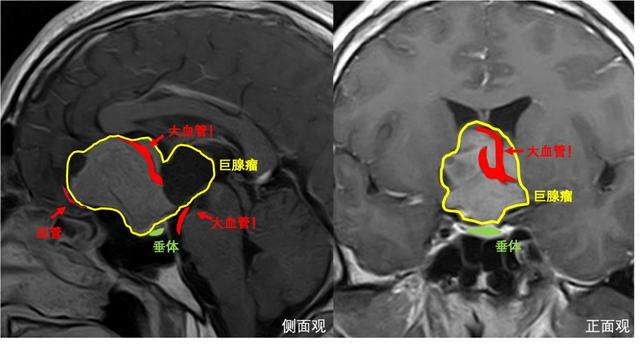

这是一颗足足有5公分大的脑瘤,更不巧的是,肿瘤形态并不规则,呈菜花状,侵犯脑内的多个腔隙,向前突向前颅底,向后生长进入脚间池,向上方长入三脑室,包绕了大脑前动脉,用“张牙舞爪”来形容真的一点也不过分。不仅如此,肿瘤周围还有视神经、下丘脑、颈内动脉等多个重要的血管和神经,手术犹如在刀尖上跳舞,稍有不慎便会“万劫不复”。

此次采用的手术方案是内镜经鼻联合开颅手术切除肿瘤,该手术方案作为“上海市可开展的新增医疗技术”由华山医院神经外科王镛斐团队率先申报,是目前国际最先进的处理复杂脑肿瘤的手术方法。以往对于此类肿瘤,都是采取先开颅手术,过一段时间后再进行经鼻手术切除,这样做病人需要经受两次手术,时间、精力和财力投入都比较大,而且开颅手术会造成疤痕粘连,为再次经鼻手术切除肿瘤造成一定困难。此次采用的“上下联合入路”同时需要两组手术医生,分别采取开颅和内镜经鼻的方法切除肿瘤,两组医生相互配合下可以实现优势互补,能最大程度地保证安全地切除肿瘤。

上午9:00,一切准备就绪,手术按照既定规划有条不紊开始。摆放好位置后,王镛斐负责内镜经鼻手术,从下方捣毁肿瘤根基,寿雪飞副教授负责开颅手术,从上方挖取肿瘤顶部。幸运的是,在药物治疗后,肿瘤血供明显减少,这让医生在切除肿瘤时更好地控制出血量,避免大量失血。对于钻进各腔隙内不易切除的肿瘤,寿雪飞通过将其向下推挤,使其暴露在视野内,王镛斐则趁机将此部分肿瘤从下方挖出,完美诠释了什么是“精诚合作”。最终,“上下会师”,开颅组和经鼻组的器械相遇,意味着肿瘤已经全部切除。